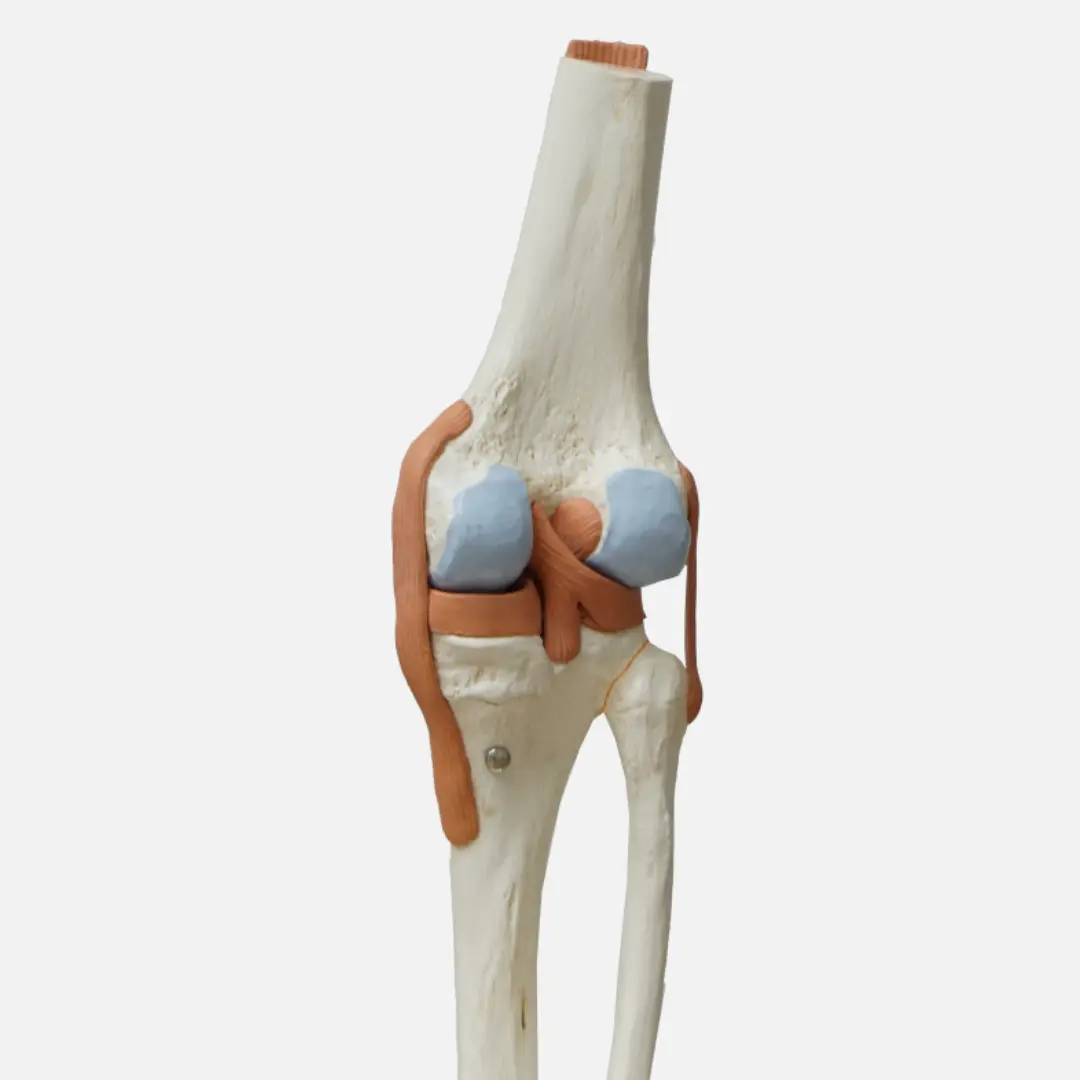

글루코사민(Glucosamine)은 우리 몸에서 자연적으로 생성되는 아미노당의 일종이에요. 주로 연골, 인대, 힘줄, 피부 등 결합 조직에 풍부하게 존재하며, 특히 관절 연골의 주요 구성 성분인 프로테오글리칸(Proteoglycan)과 히알루론산(Hyaluronic acid)의 중요한 재료가 됩니다.

연골은 관절에서 뼈와 뼈가 직접 부딪히는 것을 막아주고, 충격을 흡수하며, 부드러운 움직임을 가능하게 하는 쿠션 역할을 합니다. 이 연골은 콘드로이틴과 함께 글루코사민을 통해 건강하게 유지될 수 있어요. 하지만 나이가 들거나, 과체중, 과도한 운동 등으로 인해 연골이 손상되거나 글루코사민 생성 능력이 떨어지면 연골이 닳아 없어지고 탄력을 잃게 됩니다. 이는 결국 관절 통증과 염증을 유발하는 퇴행성 관절염으로 이어질 수 있어요.

- 연골 구성 성분 보충: 연골의 주요 구성 요소인 프로테오글리칸과 히알루론산 생성을 돕습니다.

- 연골 손상 억제: 연골을 파괴하는 효소의 활성을 억제하여 연골 손상을 늦추는 데 기여할 수 있습니다.

- 관절 윤활액 생성 촉진: 관절액은 관절의 마찰을 줄여 부드러운 움직임을 돕는데, 글루코사민이 이 생성에 기여할 수 있습니다.